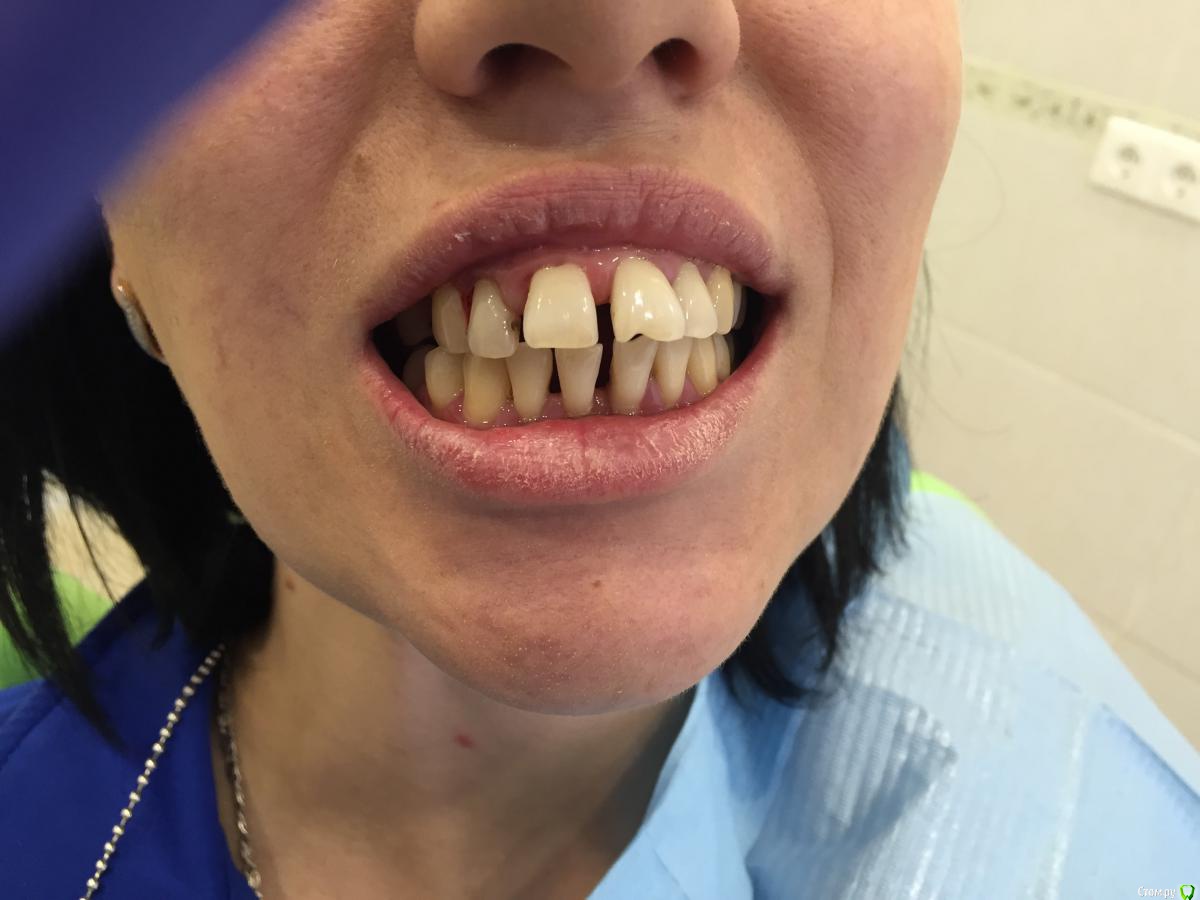

Денис777 Опубликовано 2 февраля, 2015 Автор Поделиться Опубликовано 2 февраля, 2015 Пациент пришел по поводу эстетического не удовлетворения своих зубов. Вееро образное расхождение фронтальных зубов,подвижность 2 степени.Нужен совет докторов кто как борется с пародонтозом,протокол лечения.P.S Извиняюсь за фото не было времени перекинуть в электронном ввиде Ссылка на комментарий

Денис777 Опубликовано 4 февраля, 2015 Автор Поделиться Опубликовано 4 февраля, 2015 (изменено) Вот Доктора!!!Вчера получилось сделать фото и скинуть нормальное орто.. Изменено 4 февраля, 2015 пользователем Денис777 Ссылка на комментарий

krokomot Опубликовано 17 февраля, 2015 Поделиться Опубликовано 17 февраля, 2015 (изменено) Вариантов много, на что настроена сам пациентка, просто терапию и ли по полной программе голивуд? Из этого и вытекает бюджет. Учитывая узуру от поедания семечек он довольно скромный. Нужны все специалисты терапевты, хирурги, ортопеды( вряли она наденет бреккеты, а без них зубы обратно не задвинешь). Лечение каналов зубов с апекальным переодонтитом, удаление зубов со значительной атрофией. Протезирование боковых и фронтального отделов + конечно же регулярная переодонтальная поддерживающая терапия. Так получится что-то более менее вменяемое, за что стыдно не будет Изменено 17 февраля, 2015 пользователем krokomot Ссылка на комментарий